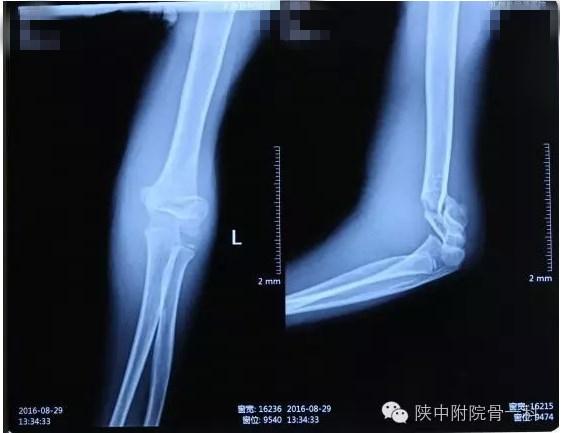

病案一:患儿XX,女,8岁,摔伤后左肘关节疼痛伴活动受限3小时入院。

诊断:Gartland Ⅱ型骨折

急诊行闭合手法复位克氏针内固定,术后X线片(下图)

术后长臂石膏维持屈肘中立位固定(下图)